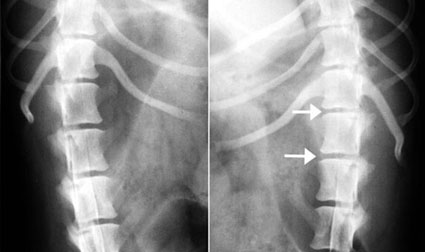

写真中段: 脊髄造影X線写真

左半分は左下斜め像、右半分は右下斜め像。

右下斜め像ので圧迫像(白矢印)が強く出ていることから、右側で椎間板ヘルニアが起こっていることがわかります。